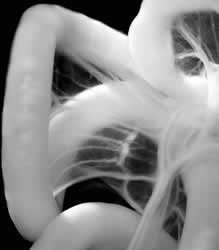

The study describes the series of molecular signals that instruct the intestines to loop counterclockwise, ensuring that they can fit untangled into the abdomen. Emerging from research on the midgut in chicken embryos, the findings suggest how other vertebrates may form other asymmetric organs, including the heart, and reveal previously unknown behavior from a gene important in cancer research.

Embryos with randomly positioned organs do not survive. Called heterotaxia, this condition’s roots trace to mutations in the gene Pitx2, which is only found in the left side of the body. After determining how Pitx2 builds organs, Kurpios’ lab found that during a critical construction day early in intestinal growth, before the looping begins, Pitx2 directs production of a protein called Daam2 only on the left side of a harness-like tissue that holds the developing intestine in place.

Ian Welsh, a graduate student in Kuprios’ lab and first author of the paper, found evidence that Daam2 was activated around the same time, suggesting a new role for Wnt in organ asymmetry. Once activated by Wnt, Daam2 directed and reorganized the growing number of intestinal cells to pack more tightly on the left side of the gut tube. This set the structure for the growing gut to start looping leftward.

gut tube forms loops